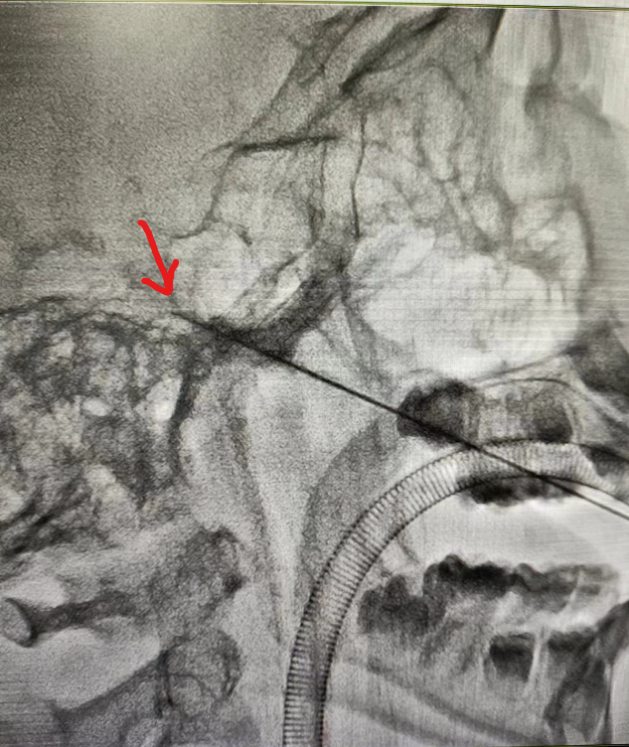

术前磁共振影像排除继发性疼痛,术中透视见穿刺针穿刺位置良好。